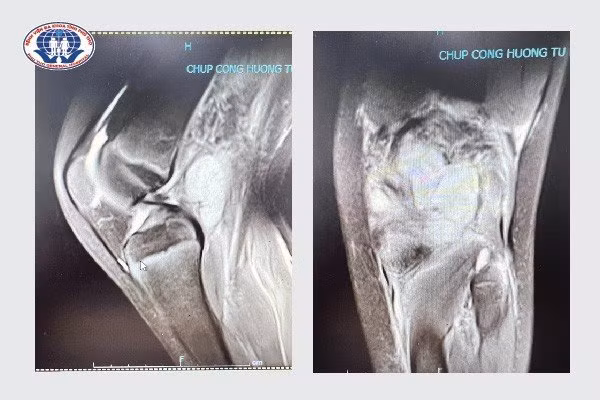

Hình ảnh chụp cộng hưởng từ vùng khoeo chân bị áp xe của bệnh nhi B.T.PHình ảnh chụp cộng hưởng từ vùng khoeo chân bị áp xe của bệnh nhi B.T.P

Tại Bệnh viện, bệnh nhi P được chỉ định thực hiện các xét nghiệm máu, cận lâm sàng như siêu âm, chụp X-quang, cộng hưởng từ để xác định rõ nguyên nhân và tình trạng bệnh. Kết quả thăm khám cho thấy bệnh nhi bị áp xe vùng khoeo chân, tổn thương diện khớp gối, các gân cơ co kéo và nguy cơ hạn chế tầm vận động khớp gối.